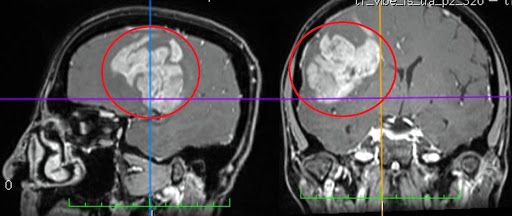

Найбільшу частину серед усіх пухлин головного мозку (приблизно 50%) становлять внутрішньомозкові гліальні пухлини.

Гліоми – це первинні новоутворення, що виникають з нервових клітин (нейронів і супутніх клітин).

Серед гліальних злоякісних пухлин найчастіше зустрічаються:

- гліобластоми (до 20%)

- та анапластичні астроцитоми (до 19%).

При цьому значно частіше зустрічаються злоякісні форми астроцитом.